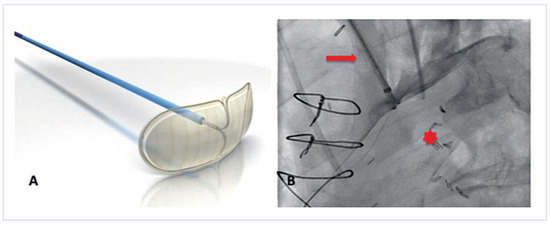

The Embrella device (Edwards Lifesciences Ltd., Irvine, CA, USA) is introduced either through the right radial or brachial artery. The concept of the device is to deflect rather than to capture emboli. Proof-of-concept was shown in the year 2010 in a first-in-human study [16]. The study confirmed the simple handling of the device, with an additional procedural time of only 13 minutes. Whether it is an atraumatic and effective device needs further investigation in a large trial. The Embrella is an umbrella-like device that consists of 2 polyurethane membranes mounted on a nitinol frame. The device is attached to a 0.035-inch nitinol delivery cable (Figure 1A). It can be folded, sheathed and loaded into a 6F long delivery sheath, which itself is placed over the right radial or brachial artery into the ascending aorta. Then the device consisting of two petals is released from the sheath. It is pulled back and positioned at the outer curvature of the aortic arch such that the petals cover the left carotid and the innominate artery (Figure 1B). In some patients it will further (partially) cover the left subclavian artery. The polyurethane membrane has 100-µm pores to ensure proper blood circulation downstream of the device.

Sitting at the outer curvature of the aortic arch, the device does not interfere with the TAVI procedures, and in particular there is no interference with the large valve delivery system. Once the procedure is terminated, the device is re-sheathed using the 6F delivery sheath.

Figure 1. The Embrella device. (A)The device consists of two petals and a delivery cable. (Courtesy of Edwards Lifesciences Ltd., Irvine, CA, USA.). (B) Once positioned at the outer curvature of the aortic arch, a contrast injection through the delivery sheath confirms proper placement. Note that the two petals of the device cover the brachiocephalic trunk and the left carotid artery. Red arrow = brachiocephalic trunk; red star = aortic lumen.